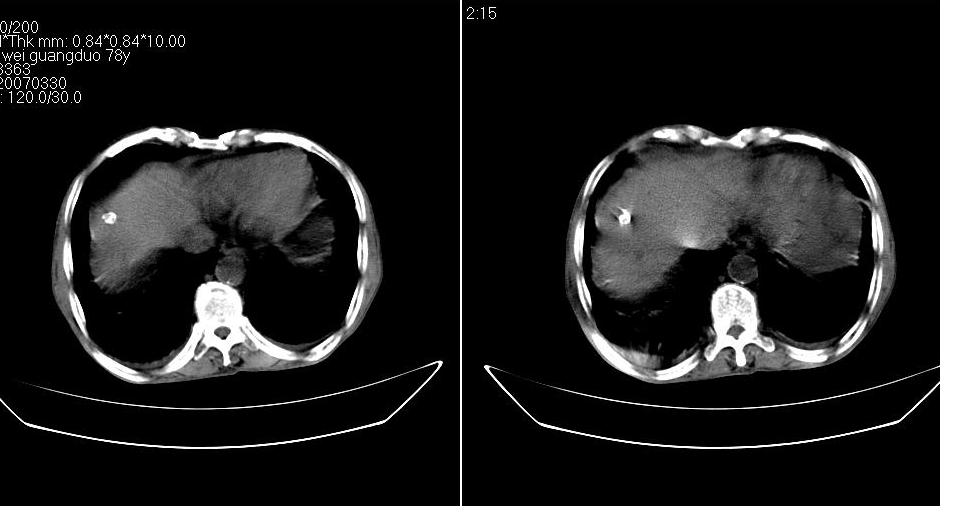

男 78岁,全身黄染,病人家属拒绝增强。

胆总管下端梗阻(原因待查)伴肝内外胆管扩张、胆囊积水。

肝周 脾周 胆囊窝内明显积液,胆囊扩大,胆囊壁模糊,肝内胆管扩张。考虑;胆囊癌周边侵润伴腹水。

1、梗阻性黄疸(胆总管下段病变或十二指肠病变)。

2、胆囊炎,腹水。

3、肝内钙化灶(寄生虫?)。